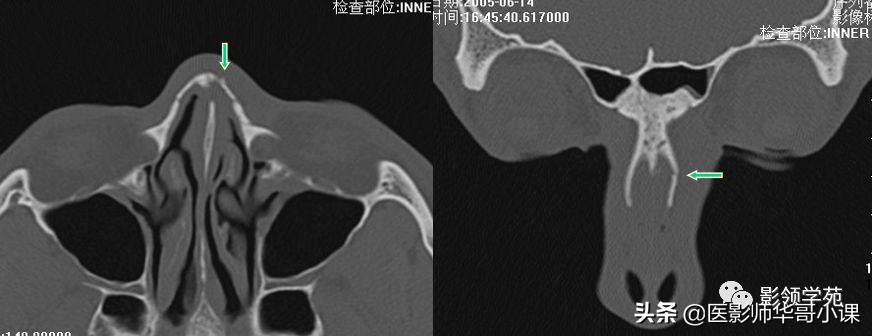

双侧鼻骨骨折

双侧上颌骨额突骨折

鼻中隔骨折

鉴别诊断

- 鼻缝

- 鼻骨孔

- 缝间骨

鼻颌缝

鼻额缝

额颌缝

鼻骨间缝